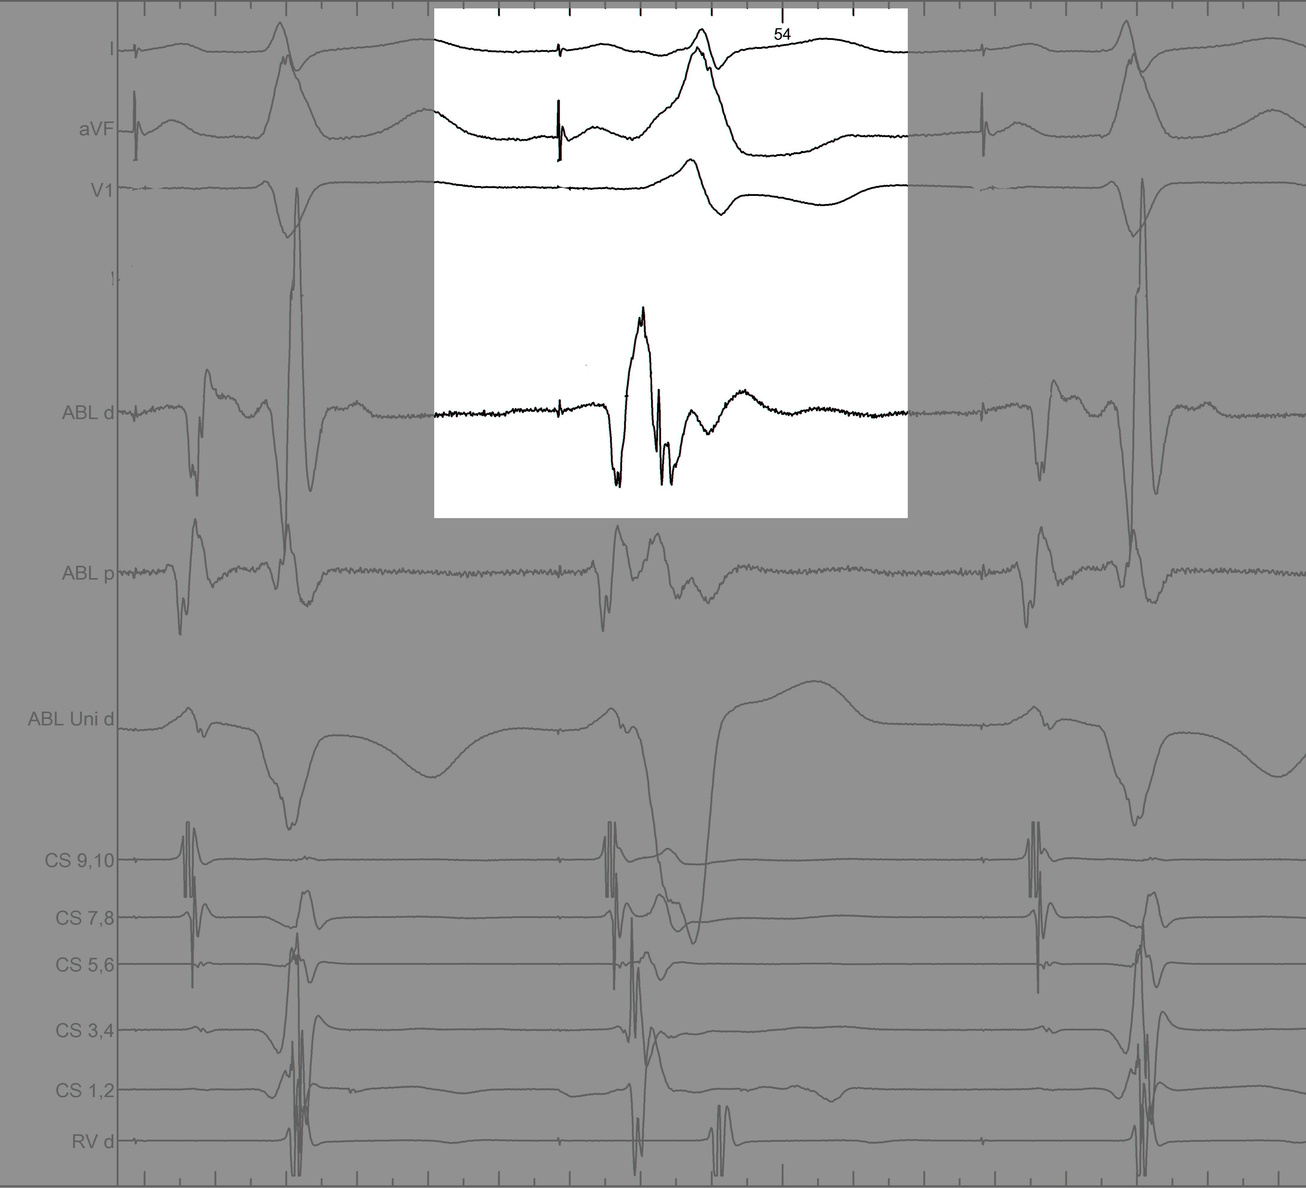

Identify components of the signal

mask3.jpg